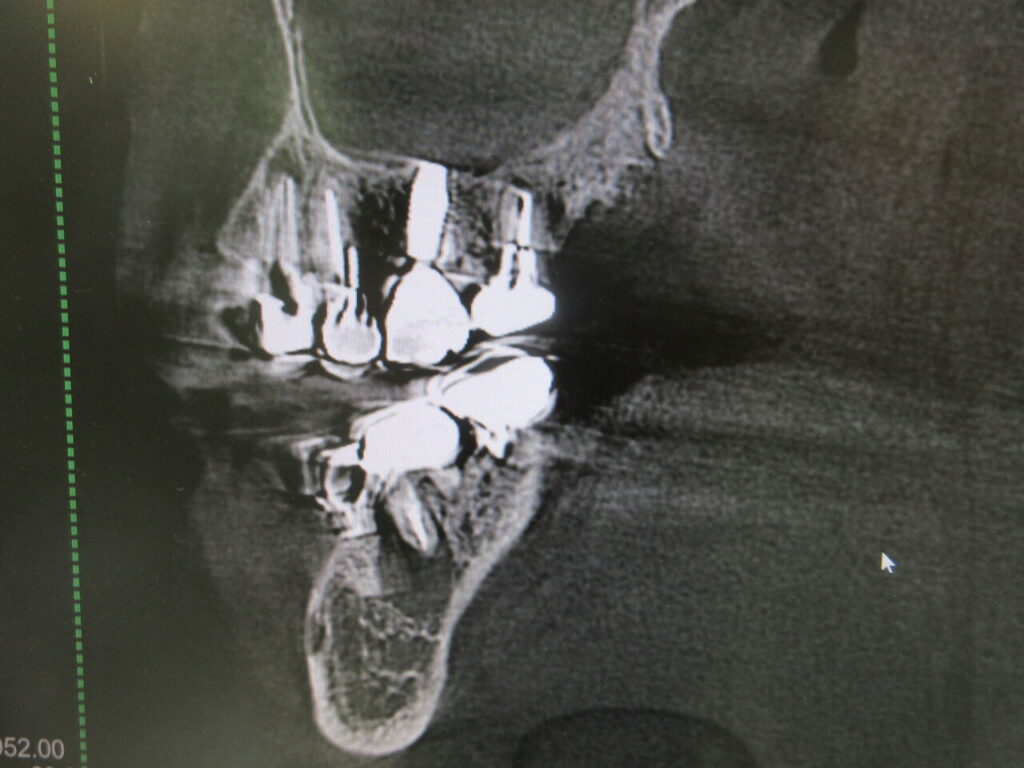

数年ぶりに来院された患者様でしたがパノラマレントゲンを撮ると下顎左側6番に骨透過像が見られます。CTで確認すると、かなり大きくおそらく手前のインプラントもだめにしてしまいます。

この場合は抜歯しかありません。定期的に来院して頂けたらかわっていたかも知れません。